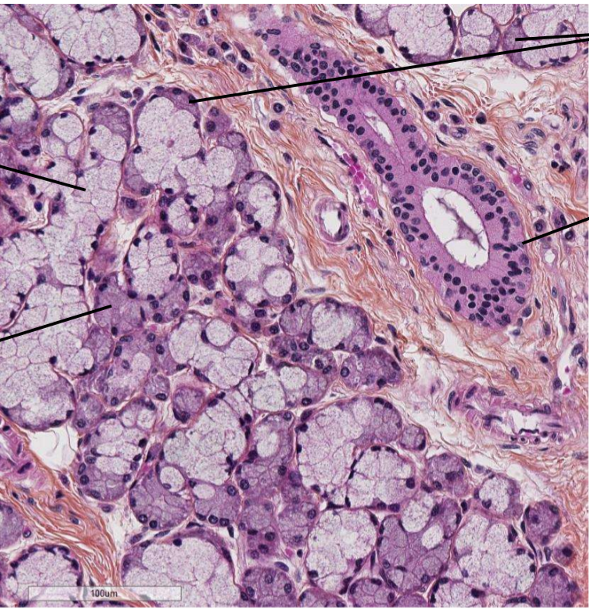

Quelle est cette lame (structure)

nomme les 3 choses délimités par les flèches

quelle coloration

A

Lame de pancréas (glande amphicrine)

Travées conjonctives, glande exocrine, glande endocrine

HES (très rose)